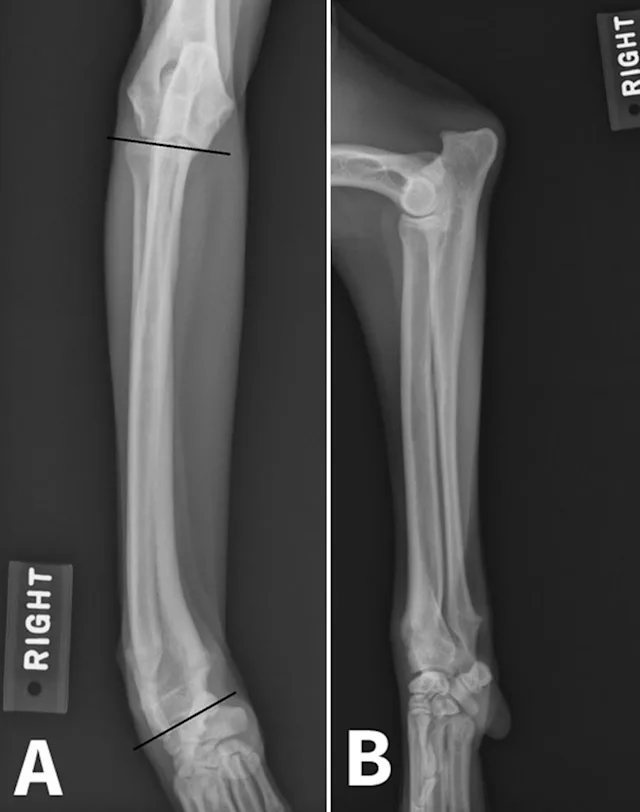

Physeal trauma is a common cause of ALD, particularly when paired bones are involved. Distal forelimb trauma in immature patients can cause a compression injury (Salter V fracture)2 to the conical-shaped distal ulnar physis, leading to premature closure of the distal ulnar physis. This results in cessation of ulnar growth. Although the radius will continue to grow in affected patients, valgus deviation, cranial bowing of the radius, and torsional deformity can typically develop as a result of the constraining effect of the ulna.3

Image courtesy of Derek B. Fox, DVM, PhD, DACVS, University of Missouri